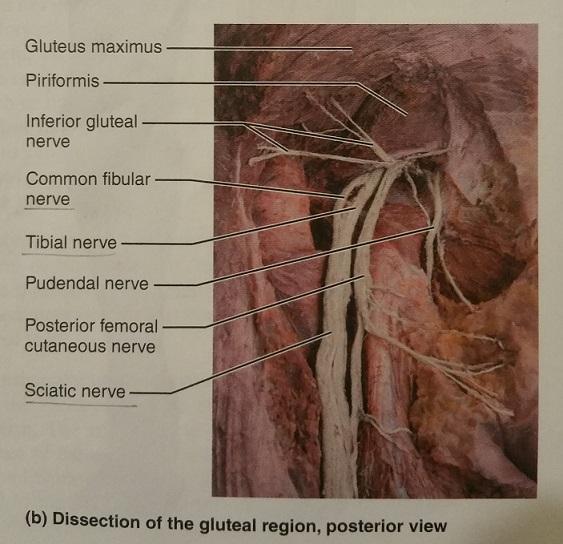

What is the major peripheral nerve of the sacral plexus?

Sciatic nerve

The sciatic nerve arises from the ventral rami of what lumbar and sacral nerves?

L4-L5 and S1-S3

What is the largest nerve in the body?

Sciatic nerve

The sciatic nerve serves which group of muscles of which body part and also, which general feature of that body part?

Serves the flexor muscles of the posterior thigh and the skin of the posterior thigh

In the popliteal region, the sciatic nerve divides into which 2 nerves?

1. common fibular nerve

2. tibial nerve

The common fibular nerve and the tibial nerve supply the muscles of which body part, and what general feature of that body part?

Supply the leg muscles and the skin of the leg

1. Give an example of a muscle served by the common fibular nerve.

2. Give an example of a muscle served by the tibial nerve.

1. Extensor digitorum longus

2. Flexor digitorum longus

The common fibular nerve arises from the ventral rami of what lumbar and sacral nerves?

L4-S2

The tibial nerve arises from the ventral rami of what lumbar and sacral nerves?

L4-S3